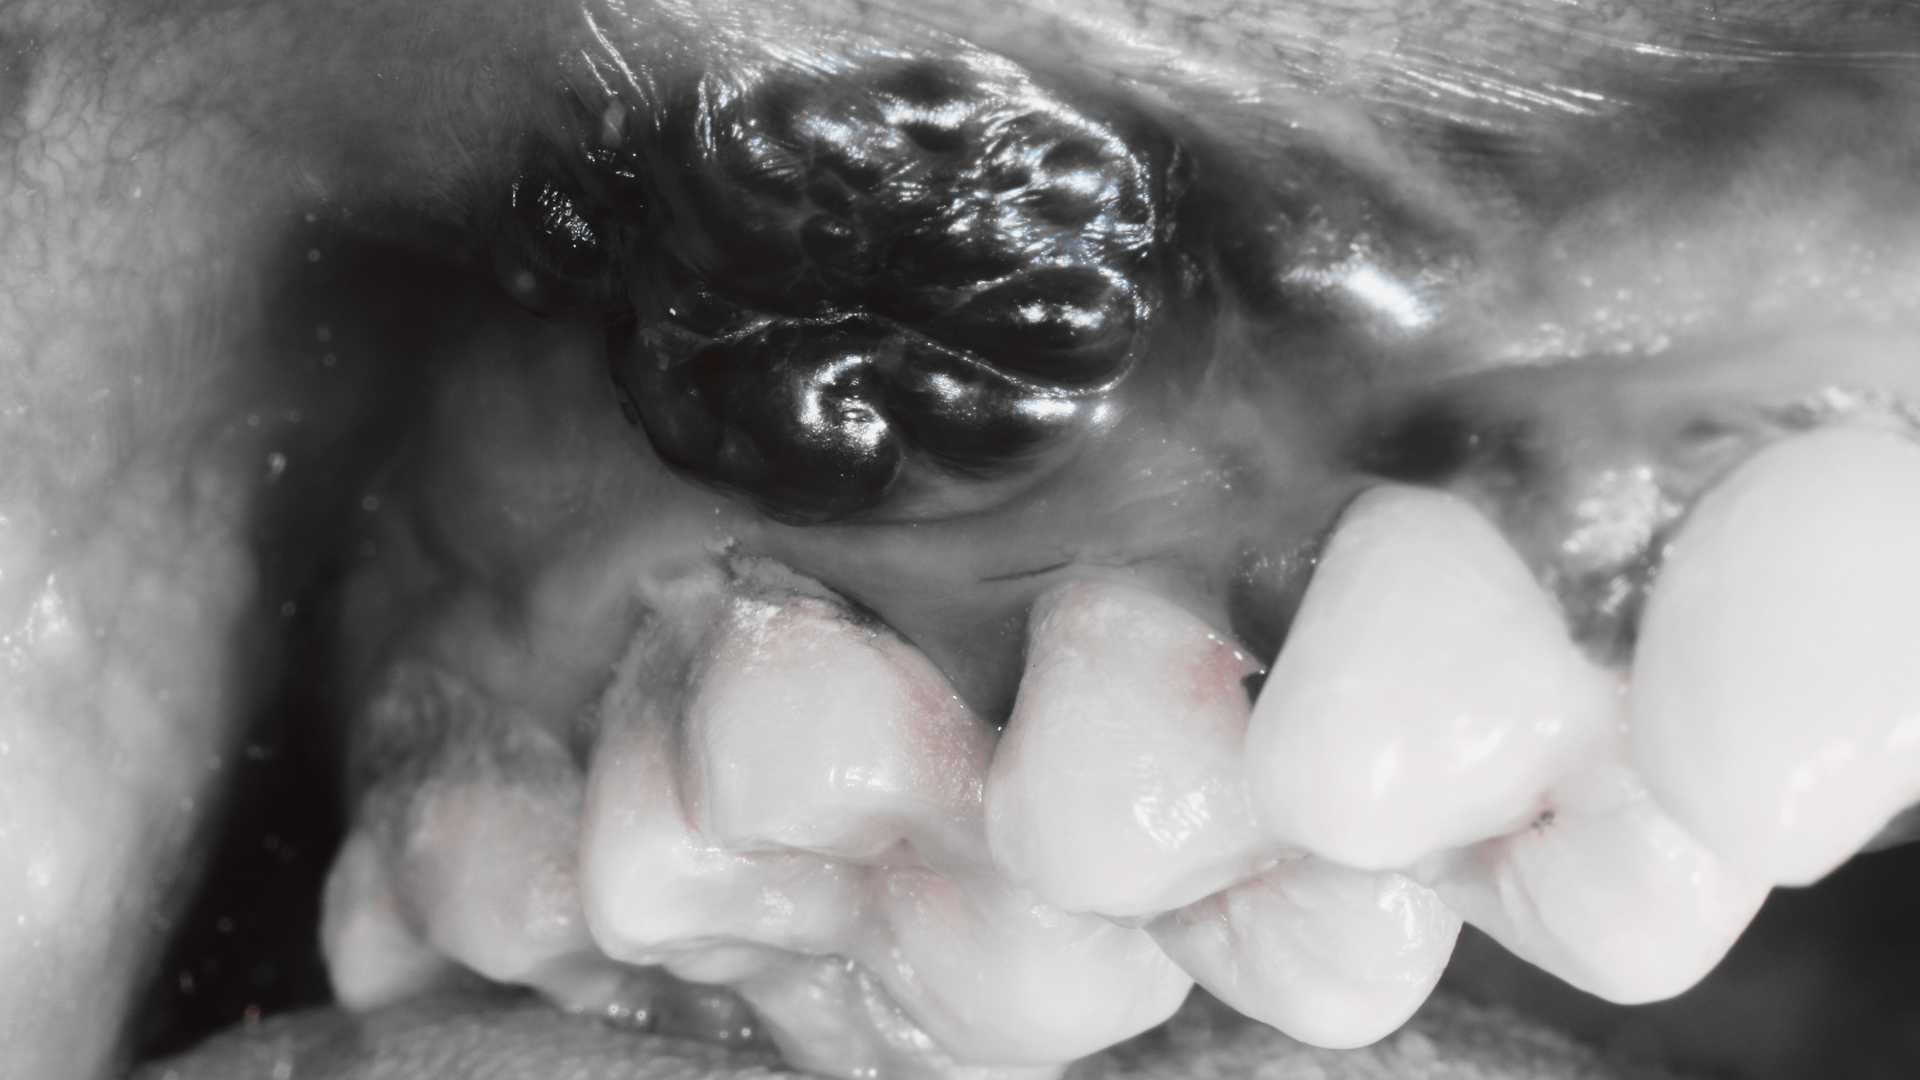

Quistes y tumores maxilofaciales

Los quistes y tumores maxilofaciales son crecimientos en la cara, cabeza y cuello, que pueden ser benignos o malignos; los quistes suelen contener líquido y se originan en tejidos dentarios o del desarrollo, mientras que los tumores son crecimiento anormal de células. Suelen detectarse por hinchazón o en radiografías y su diagnóstico implica imágenes y, a menudo, una biopsia para análisis patológico. El tratamiento puede ser la extirpación quirúrgica, que es el método principal para curar estas lesiones.

Biopsias maxilofaciales

Las biopsias maxilofaciales son procedimientos para extraer tejido o células de la boca, cara o cuello para un análisis de laboratorio, con el fin de diagnosticar lesiones sospechosas de tumores, quistes u otras enfermedades bucales y maxilares. Las indicaciones comunes incluyen lesiones que no se resuelven en dos semanas, crecen rápidamente, presentan características malignas (como ulceraciones persistentes o induración), o causan dolor crónico. Los tipos de biopsia varían, desde aspiración con aguja fina (BAAF) hasta biopsias con bisturí, seleccionándose según la lesión para obtener un diagnóstico preciso y guiar el tratamiento.